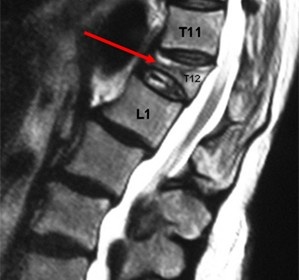

Патологический перелом 12 грудного позвонка.